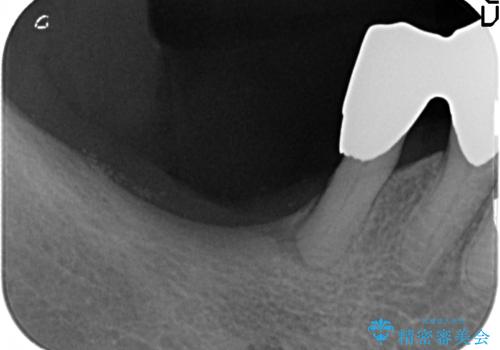

- 下の前歯(左下2)と奥歯の動揺がひどくなってきたことを主訴に来院された患者様です。

精査したところ、前歯の咬み合わせが反対になっていること、下の奥歯(下顎両側67)が4本欠損していることから動揺が生じていました。

入れ歯も抵抗があるとのことから、相談を重ね、今の状態では保存不可能な下の前歯(左下2)を抜去し、ブリッジや連結補綴により動揺を抑えることにしました。

下顎大臼歯が欠損したままで今ある歯に負担がかかりやすいことから、長期的予後は保証できないことをご理解頂いた上で治療を行いました。